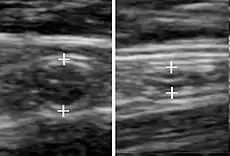

Compression ultrasonography is when the probe is pressed against the skin. This can bring the target structure closer to the probe, increasing spatial resolution of it. Comparison of the shape of the target structure before and after compression can aid in diagnosis.

It is used in ultrasonography of deep venous thrombosis, wherein absence of vein compressibility is a strong indicator of thrombosis.[94] Compression ultrasonography has both high sensitivity and specificity for detecting proximal deep vein thrombosis in symptomatic patients. Results are not reliable when the patient is asymptomatic, for example in high risk postoperative orthopedic patients.[95][96]